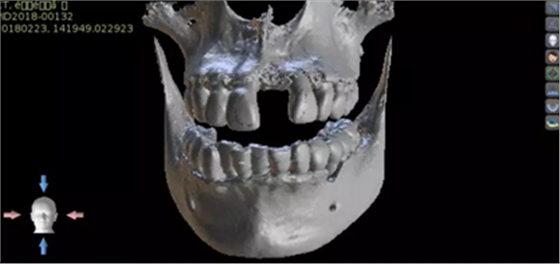

1.術(shù)前CT

2.術(shù)前植體設(shè)計(jì)

3.術(shù)前導(dǎo)板設(shè)計(jì)